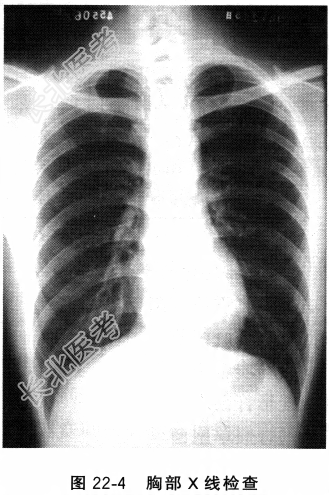

- [材料题] 患者,男性,63岁。因“反复咳嗽、咳痰4年,气喘6个月,加重1周”来诊。患者多于秋冬季发病,每年持续2~3个月,近6个月来发作时常伴呼吸困难。1周前受凉后出现畏寒、发热、咳脓痰,无尿少、双下肢水肿。既往有“气管炎”病史,吸烟史30年。查体:体温37.9℃,意识清,口唇无发绀,气管居中,桶状胸,双肺散在哮鸣音,肺底部有湿啰音。心率83次/分,心律齐,未及病理性杂音,腹软无殊,双下肢无水肿。血常规:红细胞4.8×1012/L,白细胞14×109/L,中性粒细胞0.86。血电解质及血气:血钠137mmol/L;血钾3.7mmol/L;血氯108mmol/L;二氧化碳分压41mmHg。空腹血糖5.2mmol/L。肝、肾功能:尿酸420μmol/L;BUN23mmol/L;血肌酐75vmol/L,谷丙转氨酶32U/1.,谷草转氨酶32U/L。肺功能测定:一秒钟用力呼气容积/用力肺活量为65%,FEV1%为63%,残气容积/肺总量为45%,支气管扩张试验(-)。胸部X线片(图22-4)。

- 多项选择题2.该患者胸部X线片的主要特征为

A、肺容积增大

B、胸廓前后径长

C、肺野透亮度增高

D、横隔位置低平

E、外周肺纹理纤细、稀少

F、右下肺可见囊状支气管扩张